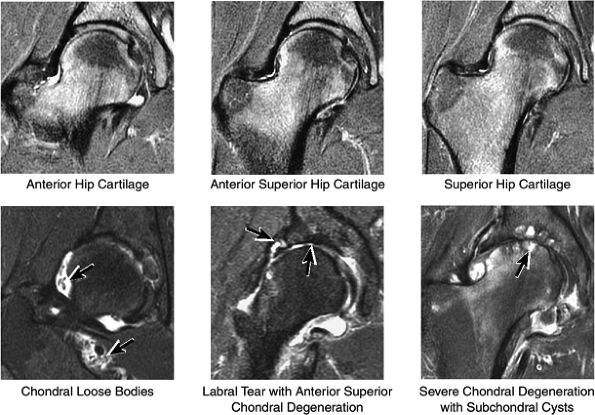

FIGURE 3.25 ● BICEPS FEMORIS The biceps femoris extends the thigh and flexes the leg in external rotation of the tibia, contributing to lateral stability of the knee. The muscles of the hamstring group (biceps femoris, semimembranosus, and semitendinosus), except for the short head of the biceps femoris, all cross the hip and the knee joint. Musculotendinous junctions extend the entire length of the muscle and serve as potential sites for strains. The short head is innervated by the peroneal branch of the sciatic nerve; the other hamstring muscles derive innervation from the tibial branch of the sciatic nerve.

FIGURE 3.26 ● SEMIMEMBRANOSUS The semimembranosus extends the thigh and flexes the leg. It is part of the hamstring muscle group (biceps femoris, semimembranosus, and semitendinosus) in the posterior thigh. Except for the short head of the biceps, the origins of the hamstring tendons are from the ischial tuberosity and are involved in ischial avulsion fractures in the young athlete.

FIGURE 3.27 ● SEMITENDINOSUS The semitendinosus, which is part of the hamstring muscle group, extends the thigh and flexes the leg. It may be used for anterior cruciate ligament reconstructions, posterolateral knee reconstructions, and tenodesis for patellar subluxation. It is the most posteromedial tendon on axial knee images at the joint line. Hip hyperflexion and simultaneous knee extension is a mechanism of injury for proximal hamstring injuries in adults and apophyseal avulsions in young skeletally immature athletes.